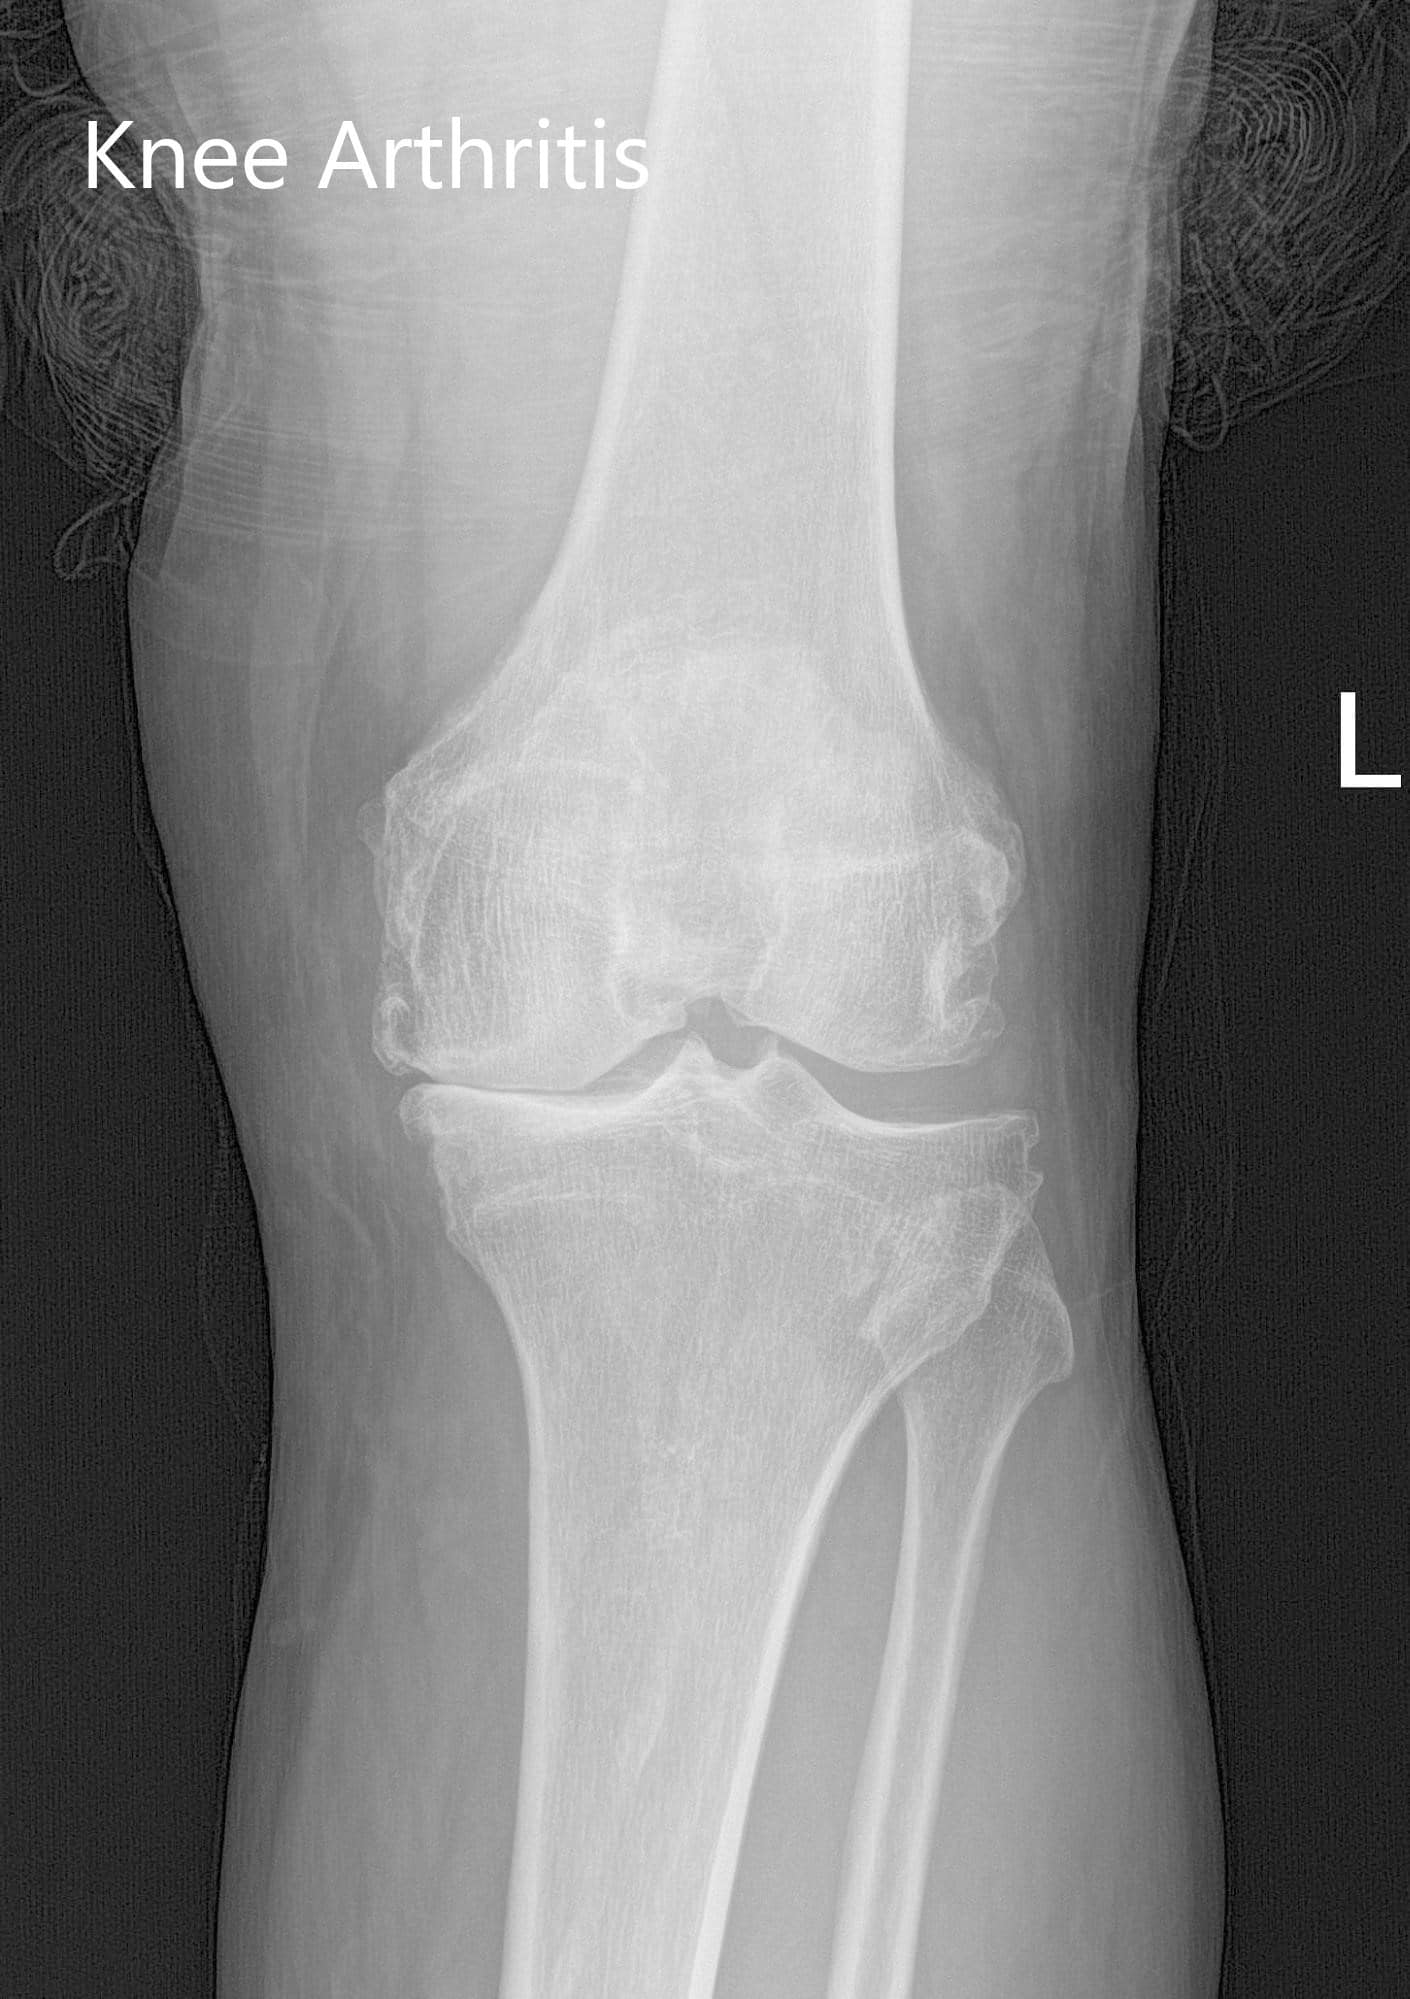

Imágenes radiográficas preoperatorias que muestran AP e imágenes laterales de la rodilla izquierda que revelan osteoartritis tricompartimental y reducción severa del espacio articular medial.

El rango de movimiento de la rodilla izquierda era completo, con una flexión final dolorosa. Las pruebas de esfuerzo coronal, sagital y rotacional para la inestabilidad fueron negativas. No hubo déficit neurológico distal. Los pulsos bilaterales de las extremidades inferiores fueron 2+ y comparables. El examen de la rodilla derecha, la cadera bilateral y los tobillos bilaterales fueron normales. Los estudios de imagen revelaron la presencia de osteoartritis tricompartimental bilateral.